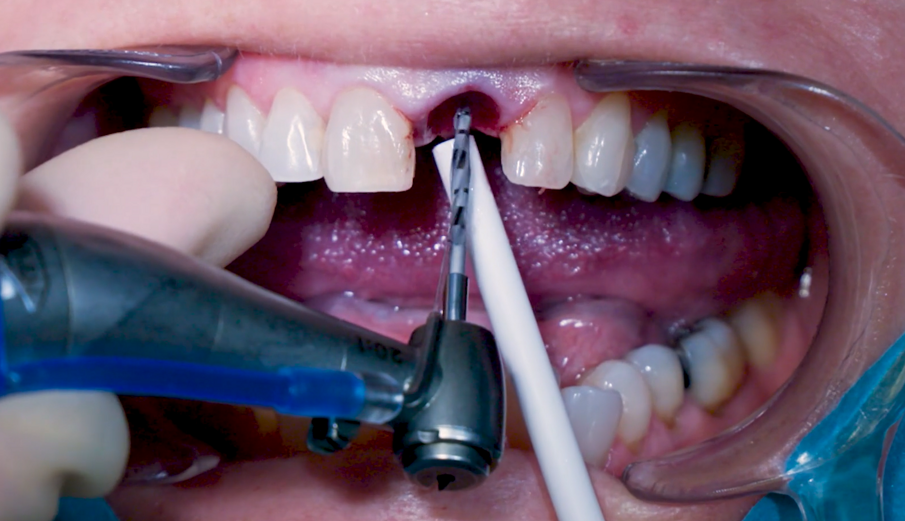

Sono state eseguite incisioni intrasulculari per liberare le fibre gengivali marginali in modo da consentire un’estrazione minimamente invasiva. L’alveolo è stato accuratamente pulito per rimuovere eventuali residui di legamenti e detriti. Particolare attenzione è stata data alla valutazione dell’integrità della parete alveolare. È stata rispettata una distanza di 3 mm tra il margine gengivale e il margine della parete vestibolare. La preparazione del sito implantare è stata considerata flusso di lavoro osseo di media densità, partendo dalla fresa appuntita in direzione della parete palatale per creare un punto d’ingresso per le frese successive, realizzando un’osteotomia per consentire una più ampia zona di ingresso dell’impianto (Fig. 5).

Fig. 5_Osteotomia iniziale con trapano ad ago.

Fig. 6_Osteotomia con trapano Ø 2,2 mm.